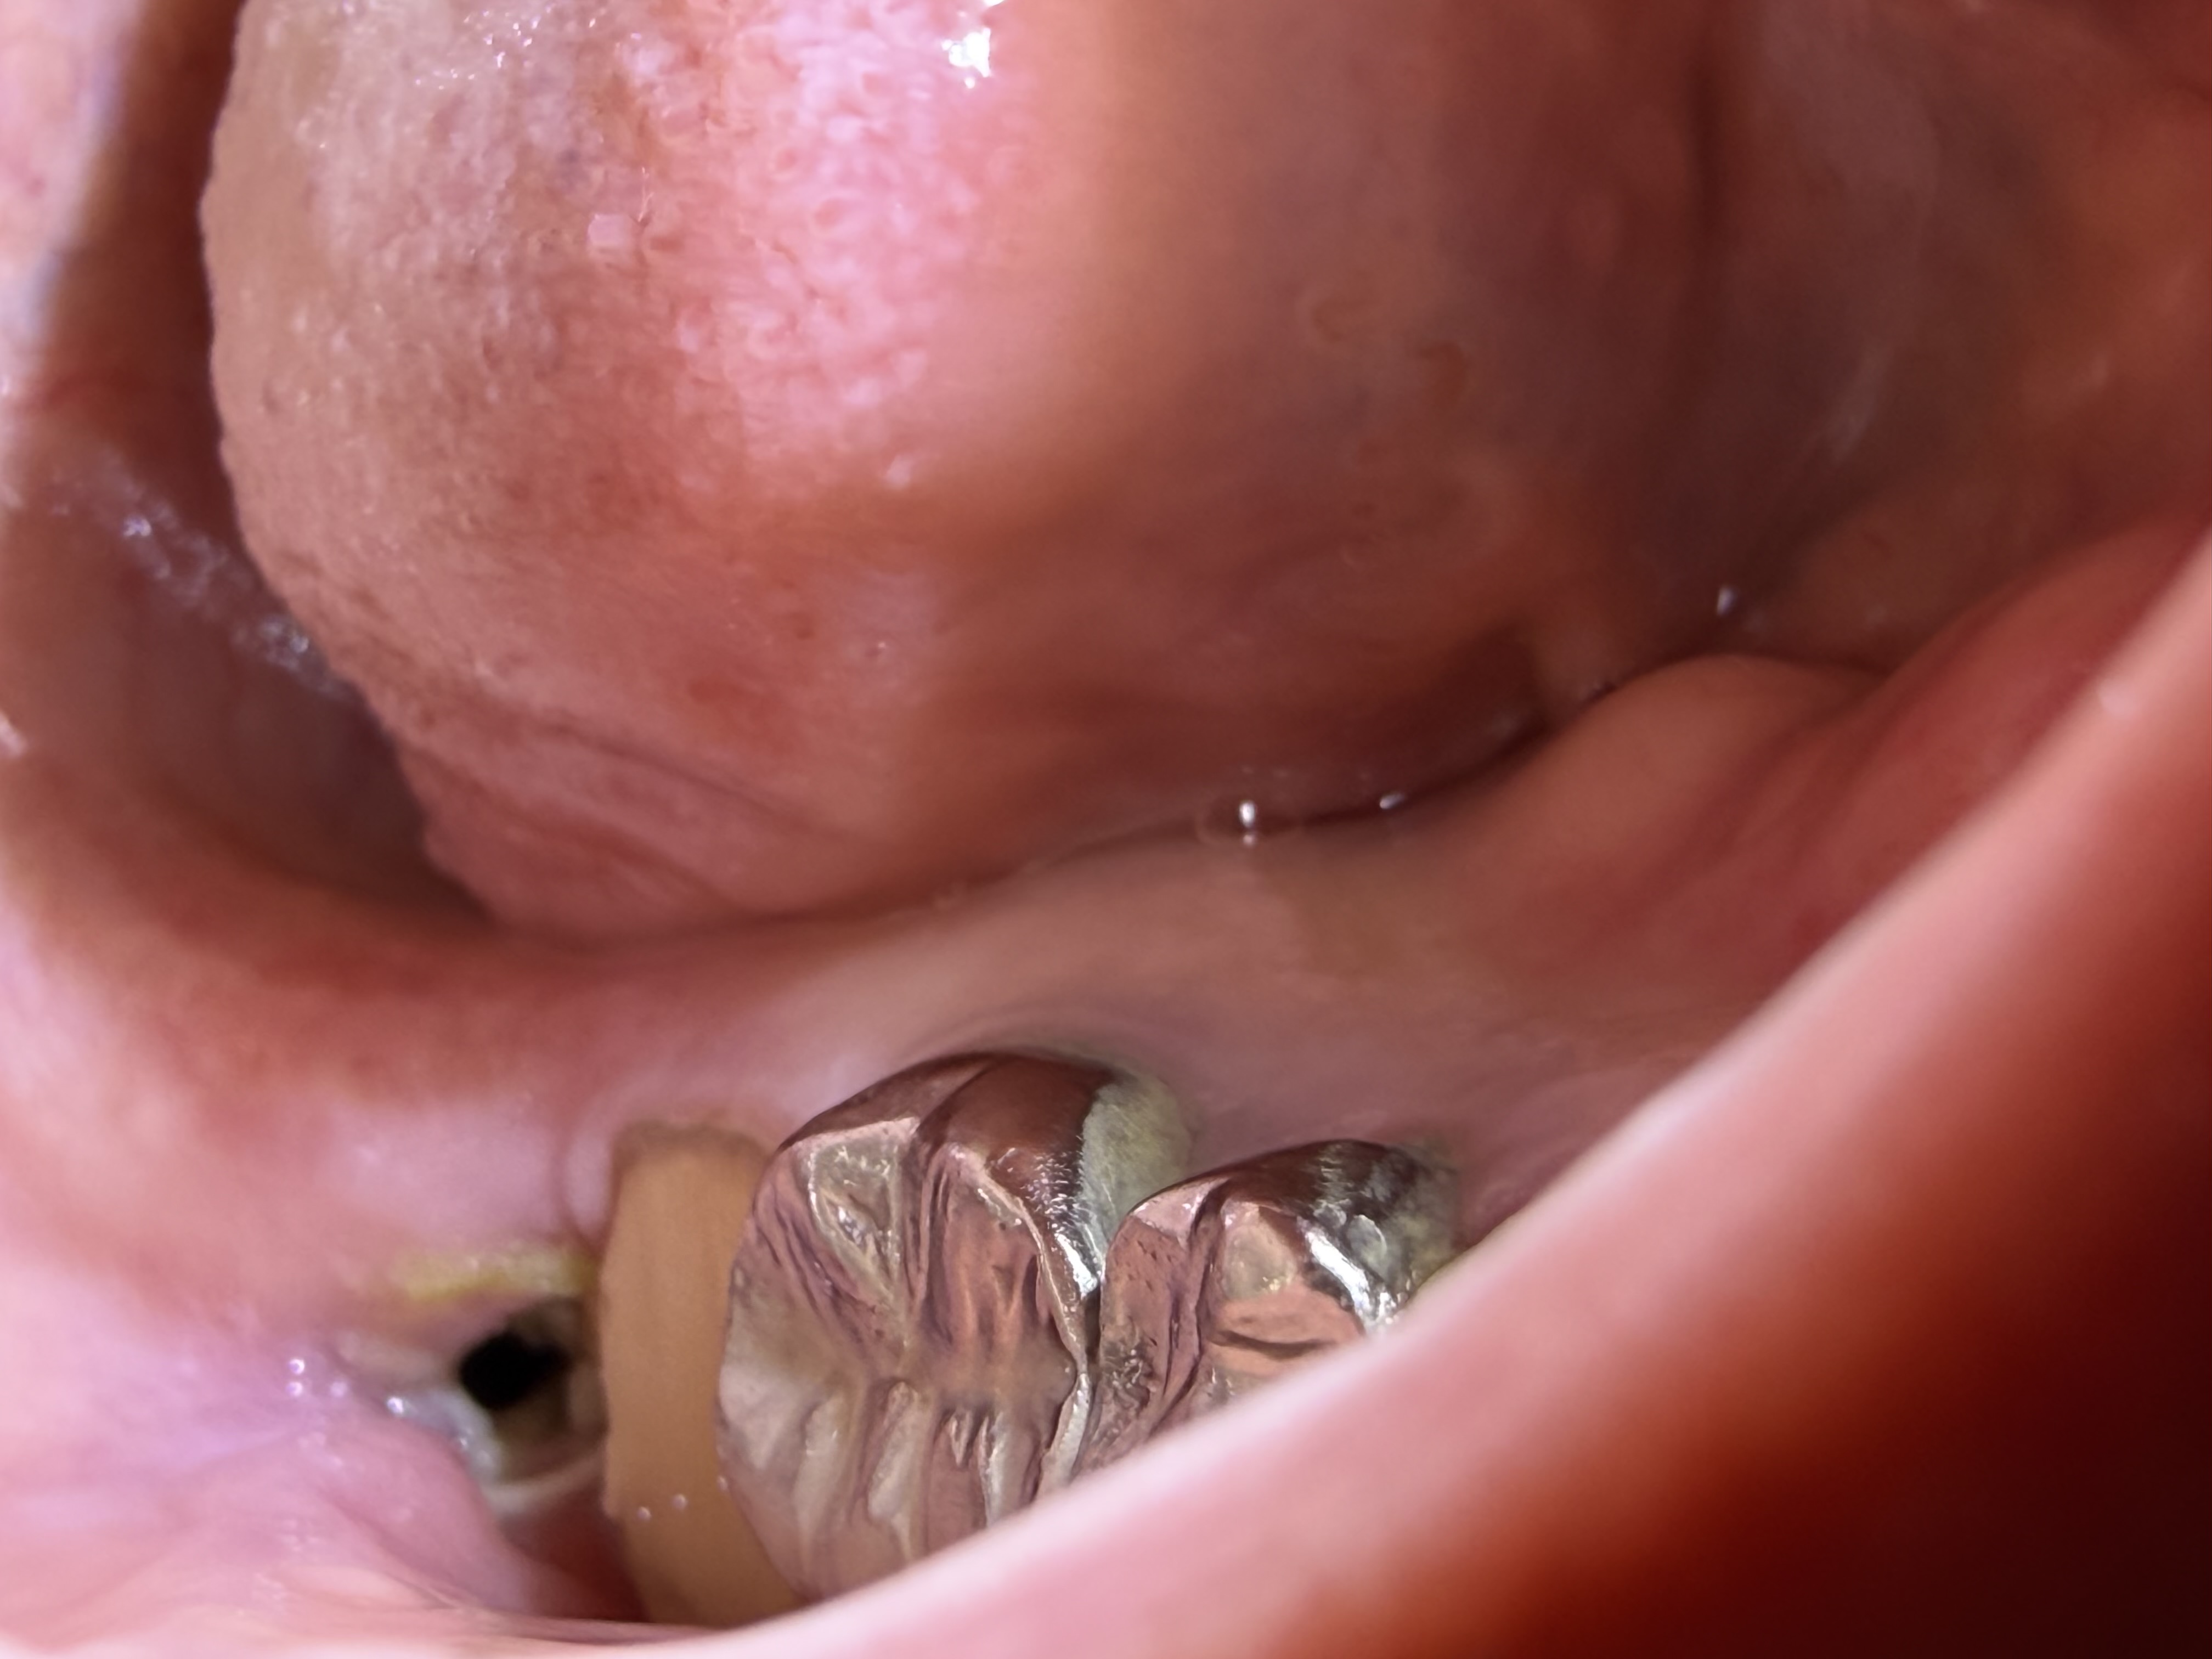

親知らずの抜歯後に血餅が取れてしまいました。

親知らず抜歯から1ヶ月以上経ちましたが、歯肉が腫れていて痛みがあります。

親知らず抜歯後、ガーゼを取った部分に穴が開いていて違和感があります。

親知らず抜歯後の痛みが長く続いています。

親知らず抜歯後、手前の歯がしみて自発痛が起きるようになりました。

親知らず抜歯後の痛みが続き、抜歯したところから匂いがあります。

親知らず抜歯後、隣の歯の歯茎が剥がれて浮いています。

親知らず抜歯後2日経ってから、ドロッとした血のようなものが出てきました。

抜歯後の部分に白いかたまりがあります。放置していても問題ないですか?

親知らず抜歯後5日目から痛みが強くなってきました。